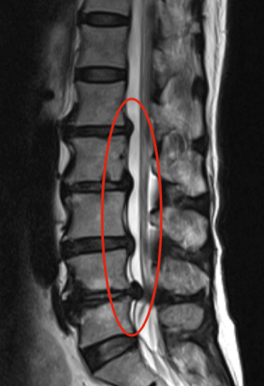

A hérnia de disco vertebral consiste na saída do seu conteúdo, o núcleo pulposo, através de uma fissura na estrutura fibrosa do disco (Fig. 2).

Fig. 2